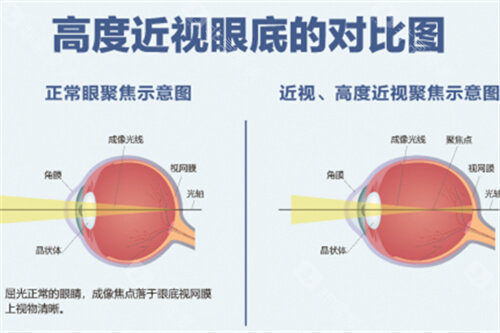

小儿斜弱视与屈光专科:早矫干预医生

谭可主治医师在青少年近视防控方面颇有建树,创新"角膜塑形镜+视觉训练"联合方案,年控制近视进展50度的达标率达76%。邵杰医师同时在小儿斜弱视治疗领域造诣深厚,其设计的"家庭视觉游戏包"能有效缩短双眼视功能重建周期至3个月。